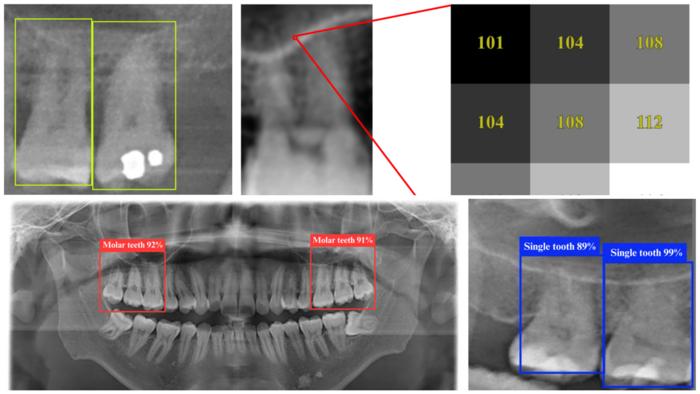

Sample dental panoramic radiographs (DPRs) as seen by the YOLO 11n deep learning model, which is able to identify tooth structures with up to 98.2% accuracy.

By training deep learning models on dental panoramic radiograph (DPR) images, the researchers found a way to detect key anatomical relationships—such as the proximity of tooth roots to sinuses—with unprecedented accuracy. The study used the YOLO 11n deep learning model, achieving an impressive 98.2% accuracy, outperforming traditional detection methods.

YOLO (You Only Look Once) is a state-of-the-art object detection algorithm known for its speed and accuracy. The YOLO 11n model, an improved version, is optimized for medical imaging tasks, enabling it to identify teeth and sinus structures with high precision in a single pass through the image. Unlike conventional diagnostic methods, which require multiple steps and expert interpretation, YOLO 11n rapidly pinpoints the affected areas in real time, making it an invaluable tool for dental professionals.